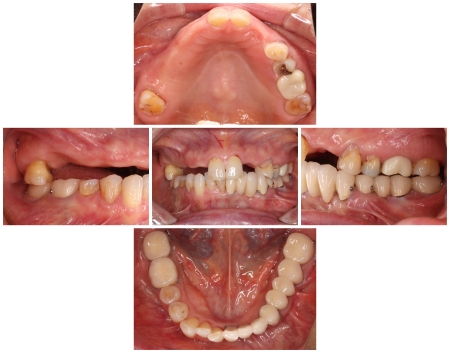

- 当院は、患者様の歯をできるだけ残し、長期的に再治療を防ぎ、質の高い健康を維持することを基本方針としています。

そのため「精密さ・耐久性・生体へのやさしさ」を重視した体制をとっており、原則として自由診療の治療をご提案しています。

一方、自由診療では個々の症例に合わせた治療設計、先進的な材料・技術の使用、再発予防を見据えた治療が可能です。